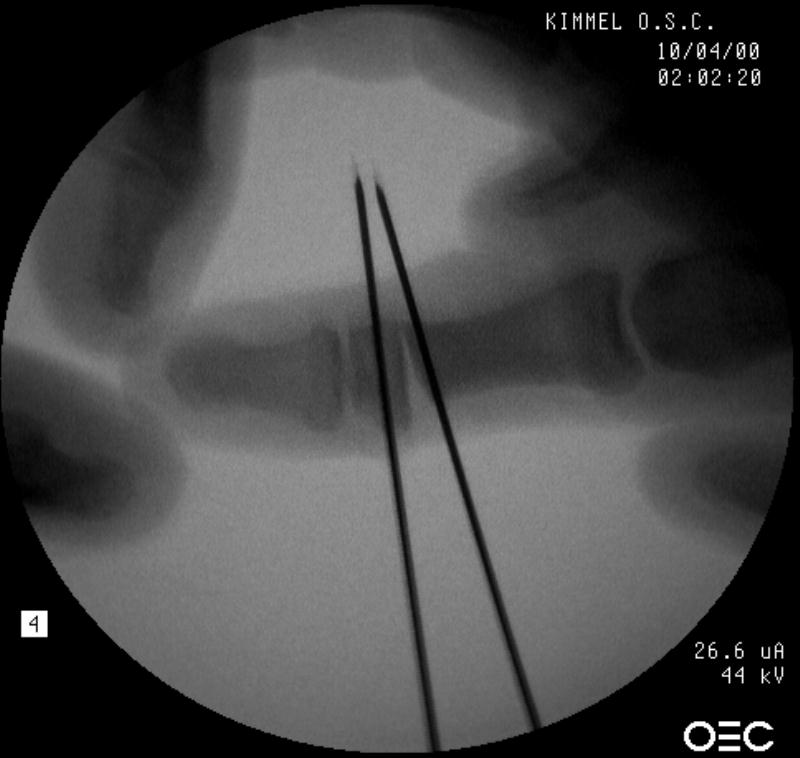

Osteotomy planning: proximal pin parallel to the proximal joint line, distal pin parallel to the distal joint line:

Click for larger image

Pins were used as saw blade alignment guides: